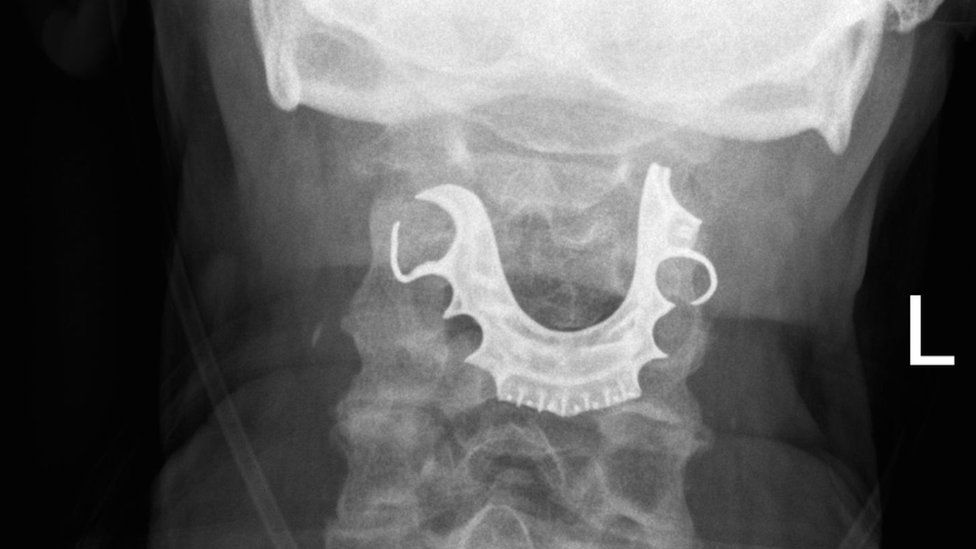

Los médicos encontraron la dentadura postiza del hombre en su laringe más de una semana después de operarlo.

Los médicos encontraron la dentadura postiza del hombre en su laringe más de una semana después de operarlo. Crédito: BMJ Case Reports 2019

Cuando el hombre regresó nuevamente dos días después, los médicos revisaron su garganta y fue entonces que encontraron un objeto semicircular sobre sus cuerdas vocales.

Y todo empezó a cobrar sentido cuando el hombre les contó que había perdido su dentadura postiza durante su operación.

Una vez que que le hallaron el objeto en la laringe, ocho días después de la primera operación, el paciente tuvo que ser intervenido nuevamente para remover la dentadura postiza de su cuerpo.